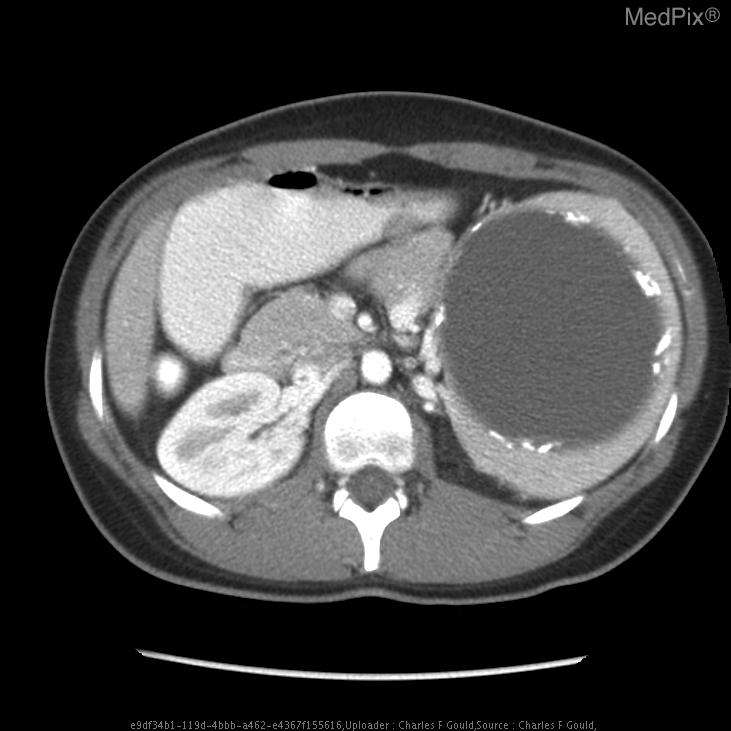

КТ-исследование абсцесса малого таза: Визуализация и диагностика

Раздел: Фотоальбом решений